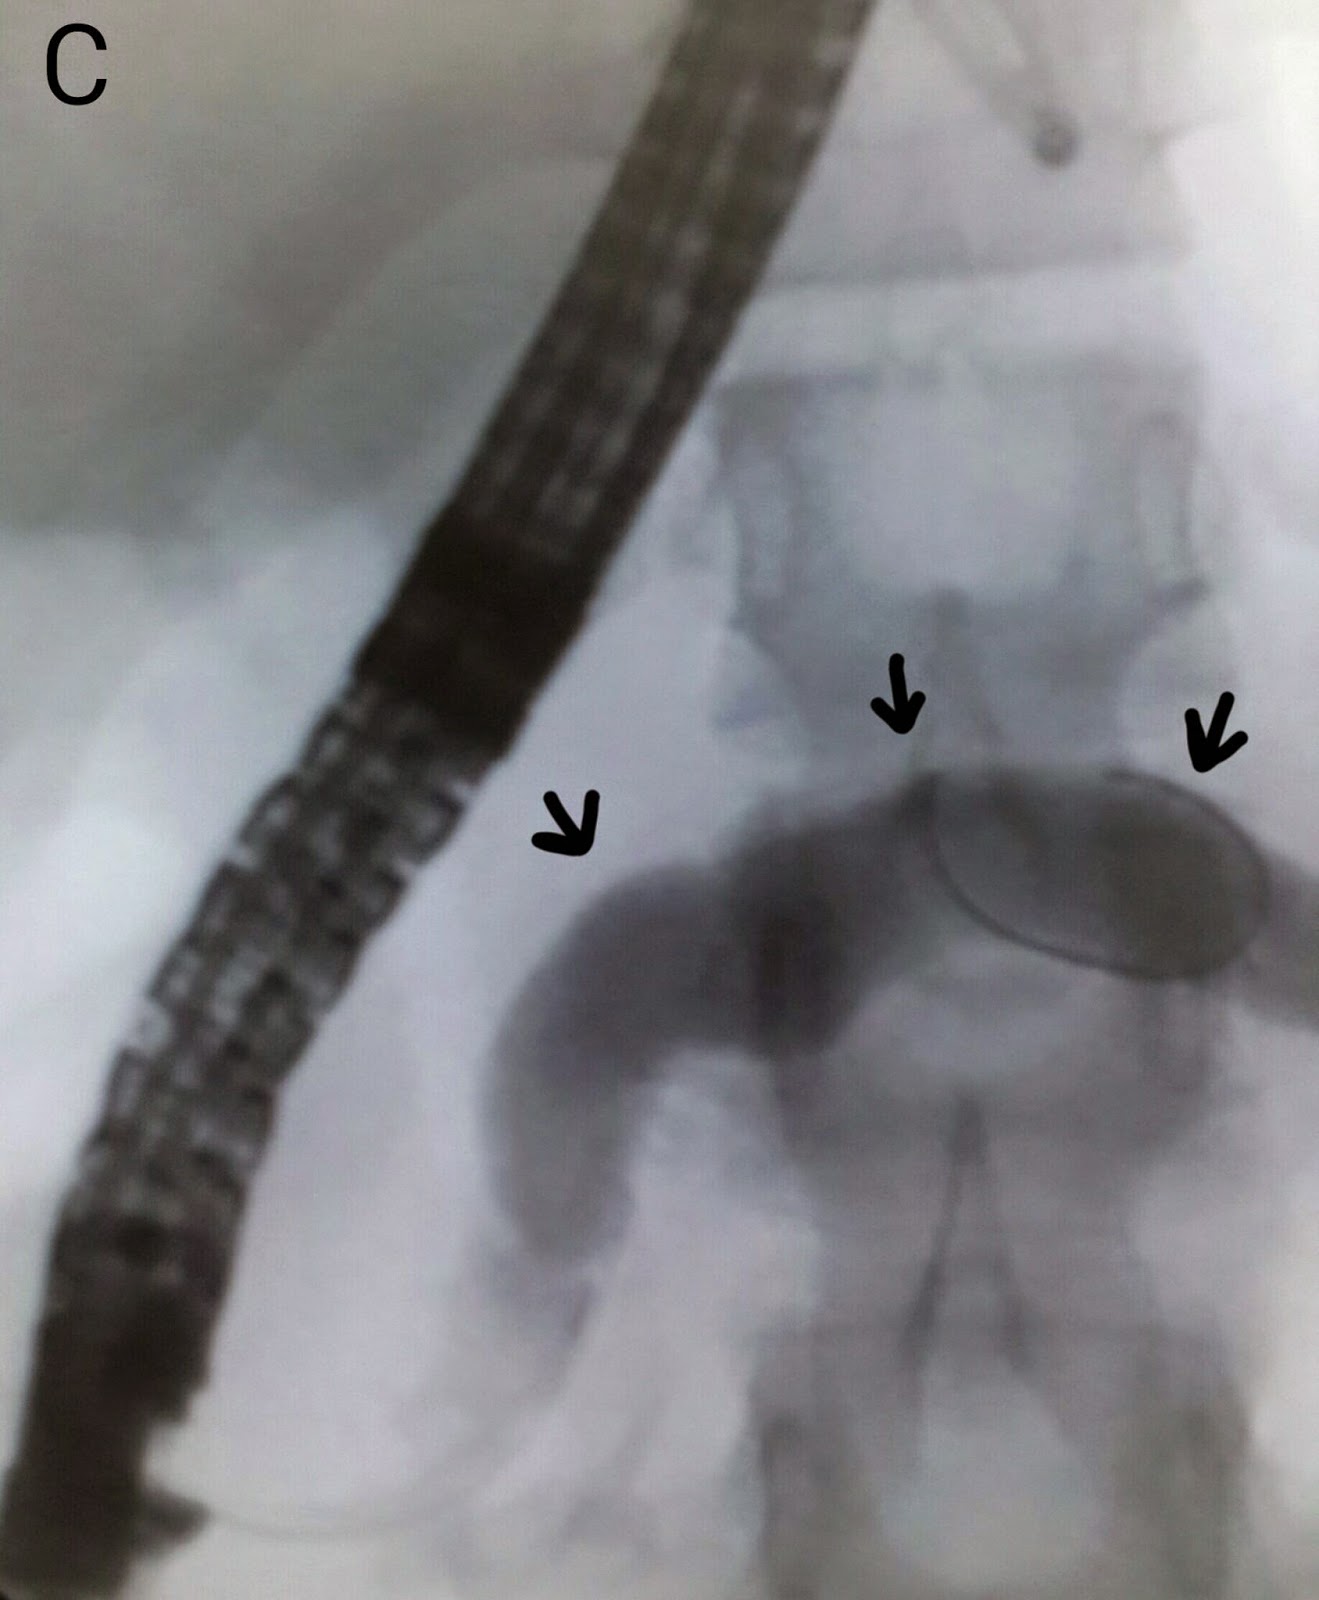

This gentleman had recently undergone a live related liver transplant. His bilirubin levels started to rise along with his alkaline phosphatase. An anastomotic stricture was suspected and confirmed on MRCP (A: red arrow shows the strictured area along the left maim duct). A guidewire was passed into the left system (B: black arrows mark the guidewire in the left ductal system). A TTS stricture dilatation balloon was manoeuvred across the affected segment and inflated to 9mm (C: black arrows indicate the balloon in the stricture site. The balloon isn't clearly visible because we haven't mixed any contrast with the saline). Repeat contrast injection some improvement in ductal filling (D). We then placed a plastic stent of 10 French diameter and 12 cm length (E: black arrows mark the deployed stent).